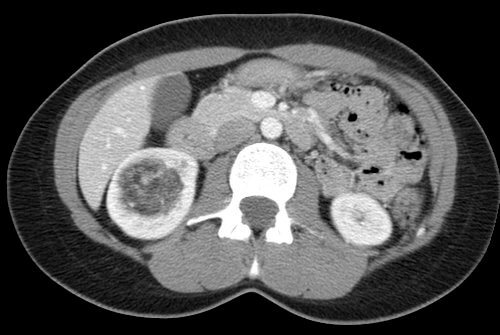

32 year old female who presents with an incidentally discovered right renal angiomyolipoma and undergoes prophylactic embolization.

Comment: This case demonstrates the classic appearance of an angiomyolipoma on CT and the hypervascularity associated with this benign tumor. The clearly seen abnormal vasculature enabled selective catheterization of the dominant supply to the angiomyolipoma and subsequent selective embolization with PVA particles. Embolization can be performed successfully with several types of particulate and/or liquid embolic agents. In this case, PVA was used successfully and no growth or viability has been seen on follow-up imaging after this procedure.